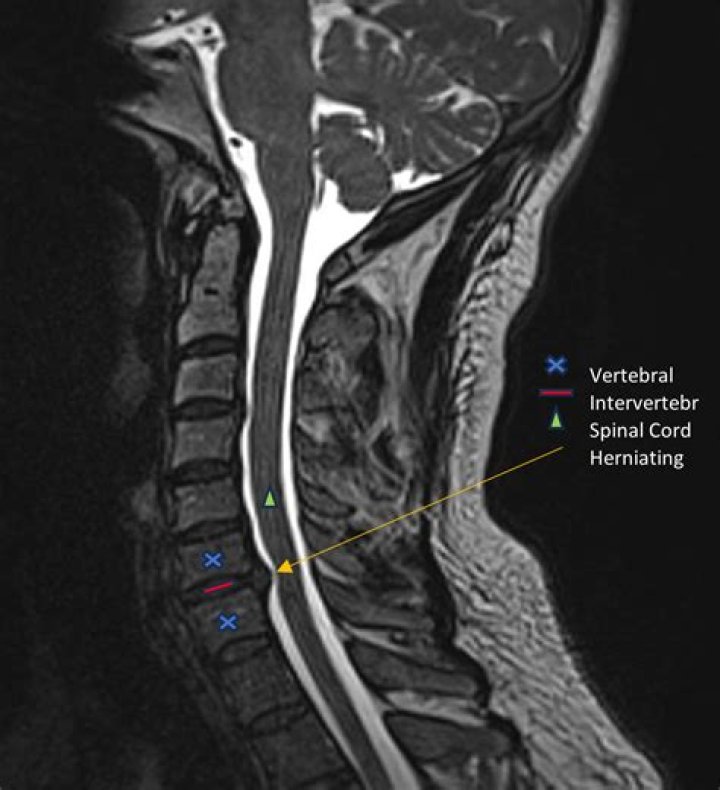

MRI scans which show soft tissues, such as nerves and discs, are generally preferred over CT scans which show bony elements. Advanced imaging can show exa...